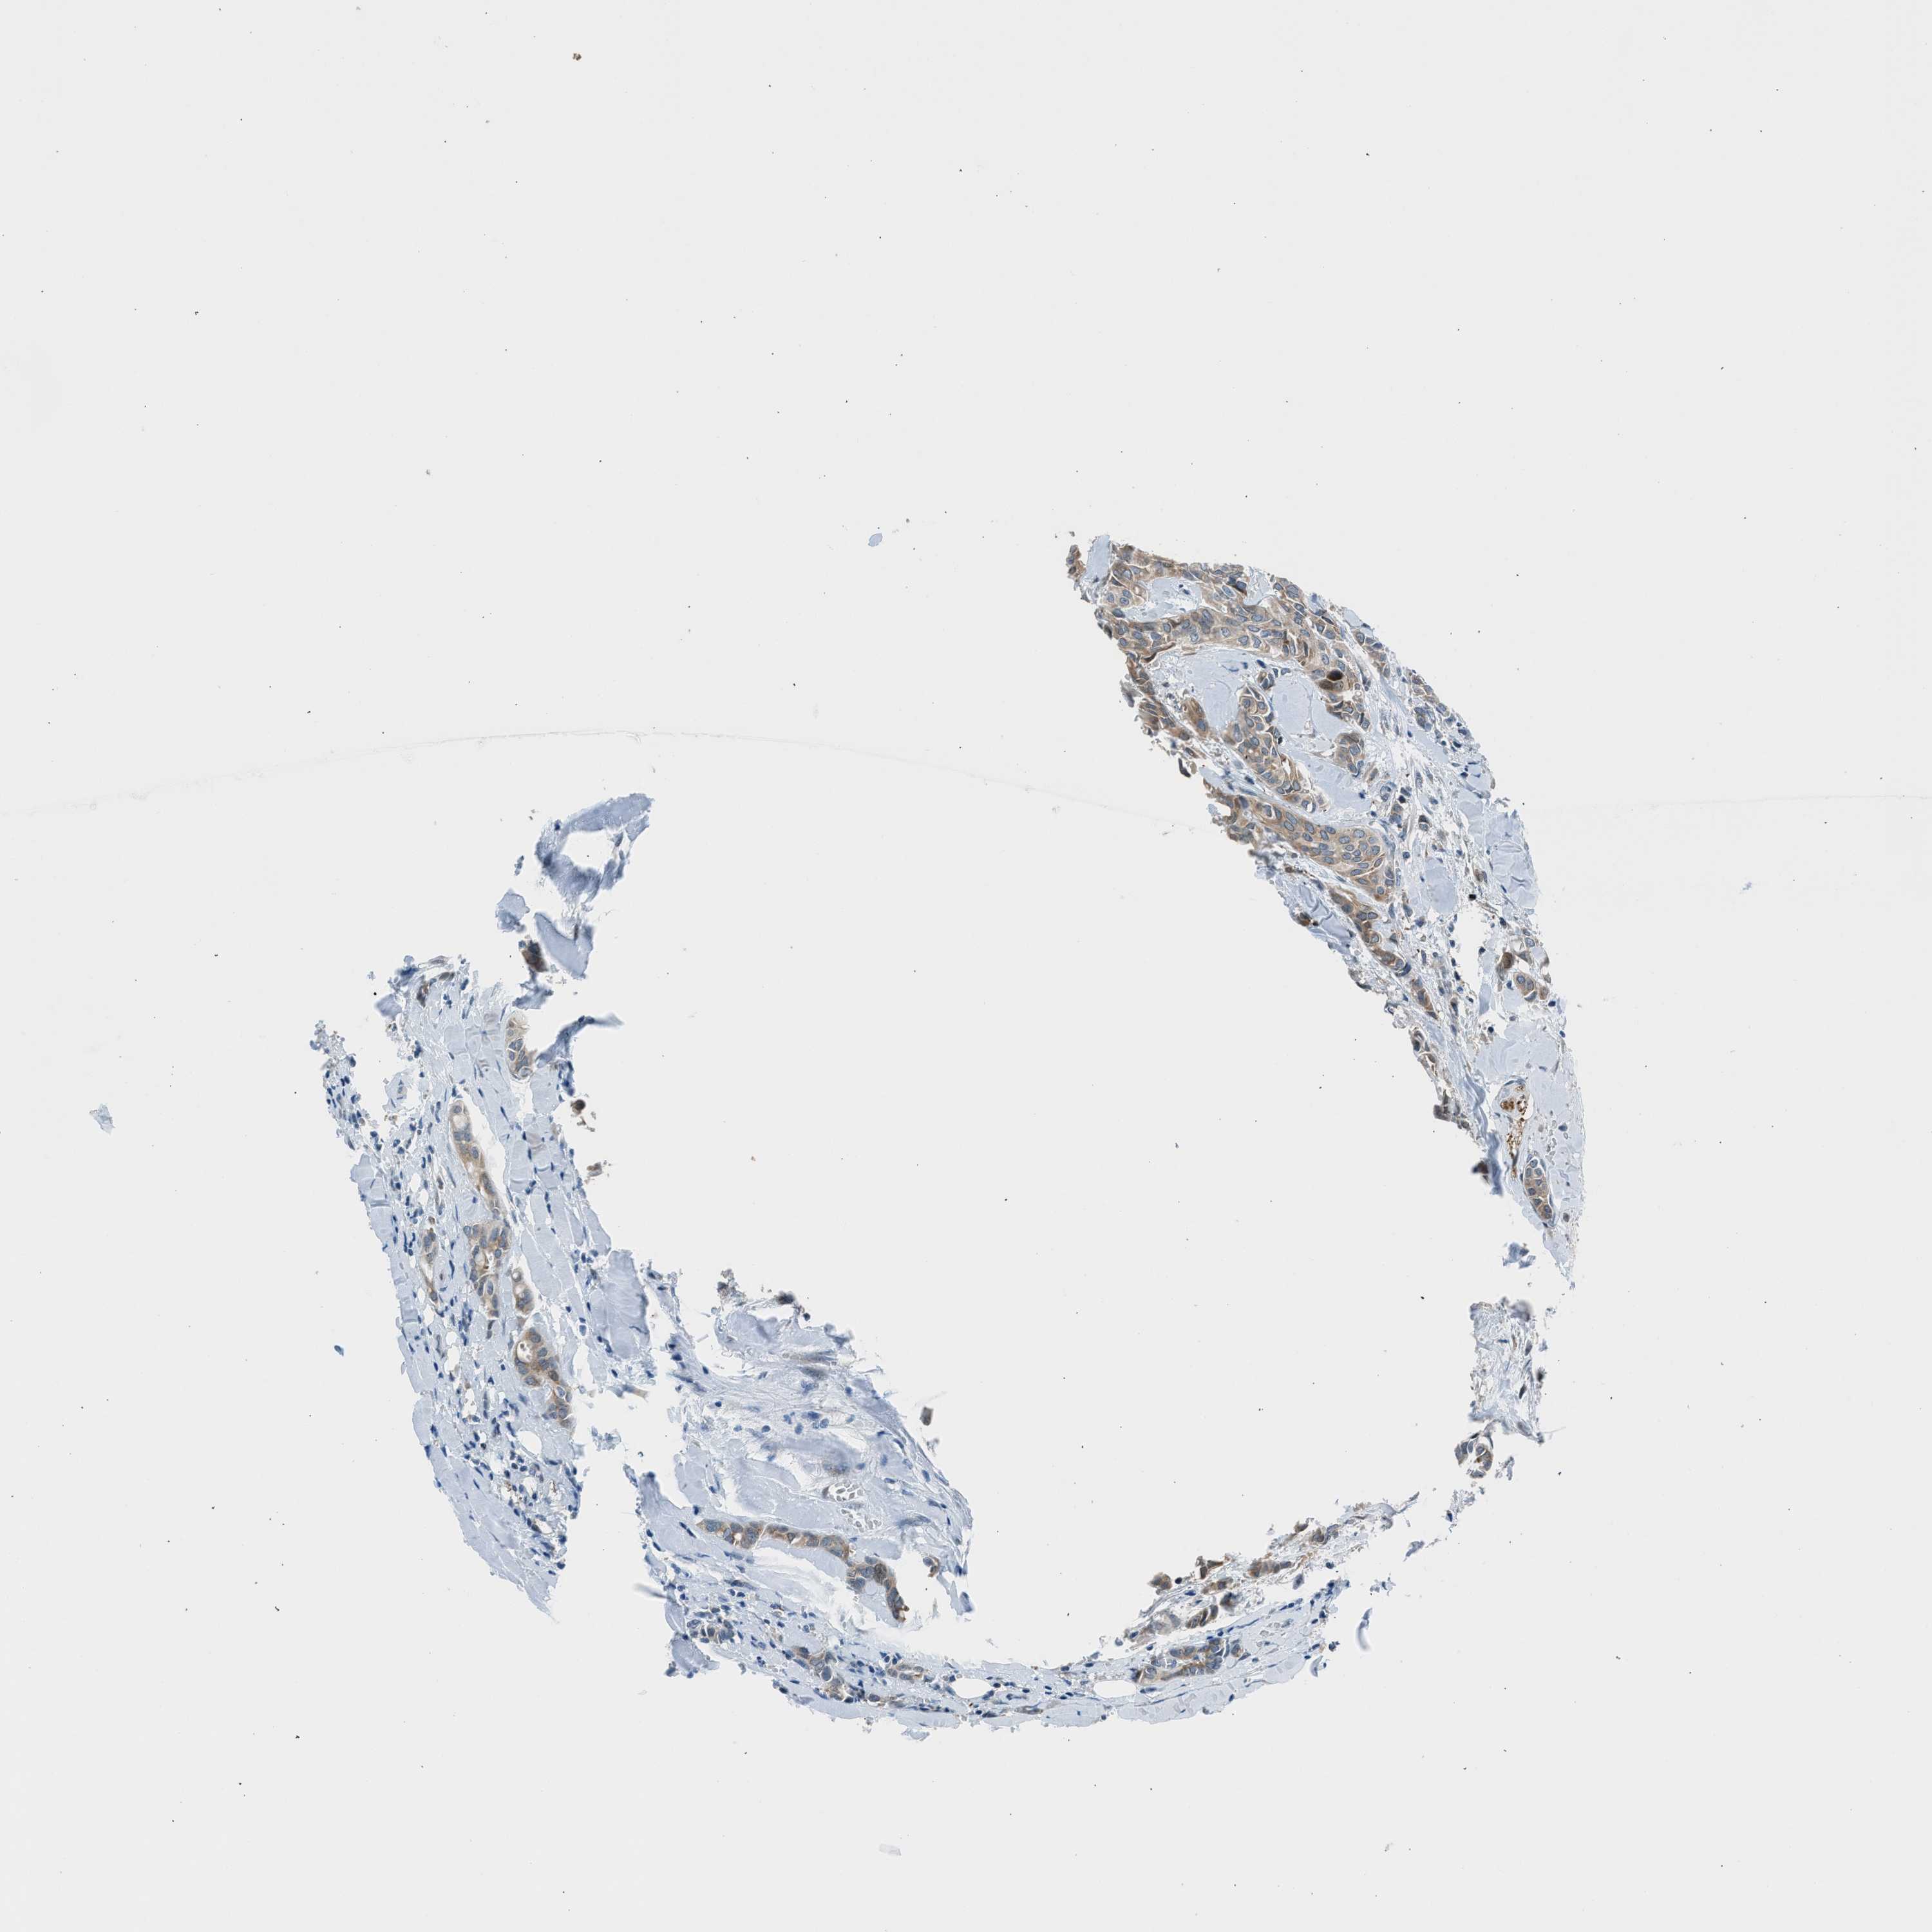

HEAD AND NECK CANCER - Protein expressioni

A mouse-over function shows sample information and annotation data. Click on an image to view it in a full screen mode. Samples can be filtered based on level of antibody staining by selecting one or several of the following categories: high, medium, low and not detected. The assay and annotation is described here.

Note that samples used for immunohistochemistry by the Human Protein Atlas do not correspond to samples in the TCGA dataset.

Antibody stainingi

Antibody staining in the annotated cell types in the current human tissue is reported as not detected, low, medium, or high, based on conventional immunohistochemistry profiling in selected tissues. This score is based on the combination of the staining intensity and fraction of stained cells.

Each image is clickable and will lead to virtual microscopy that enables deeper exploration of all samples and also displays staining intensity scores, fraction scores and subcellular localization as well as patient and tissue information for each sample.

Antibody HPA016812

Staining

High

Medium

Low

Not detected

Intensity

Strong

Moderate

Weak

Negative

Quantity

>75%

75%-25%

<25%

None

Location

Nuclear

Cytoplasmic/membranous

Cytoplasmic/membranous,nuclear

Squamous cell carcinoma, NOS

Squamous cell carcinoma, metastatic, NOS

Adenocarcinoma, NOS